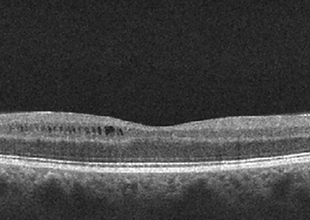

Patient Presentation: A 23-year-old obese female was diagnosed with idiopathic intracranial hypertension (IIH) and referred to neurosurgery for ventriculoperitoneal shunt. A baseline ocular examination was performed prior to the procedure.

On examination, vision was 20/200 in the right eye, and 20/40 in the left eye. There was a right relative afferent pupillary defect. Slit lamp examination was normal.

A dilated fundus examination was performed demonstrating the following: